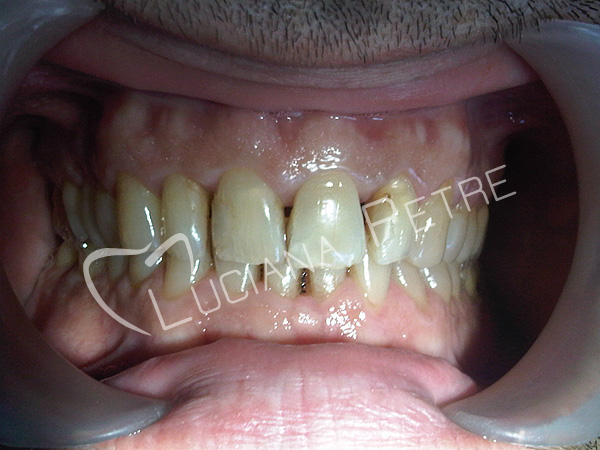

Obturatii nefizionomice pe

dintii frontali

Estetica rezolvata cu coroane din

ceramica pe zirconiu